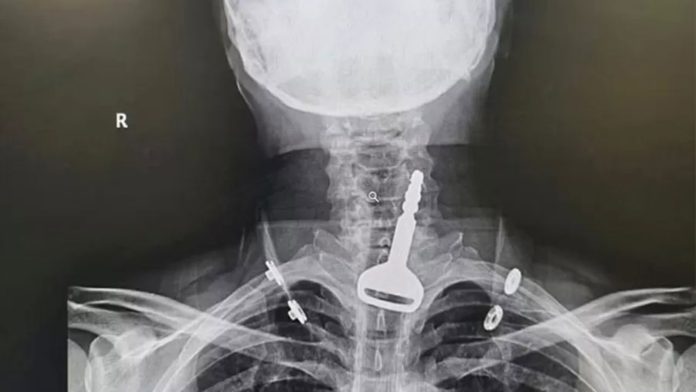

Homem se esconde da polícia em freezer, fica preso e morreO objeto ficou entalado nas vias respiratórias, entre a traqueia e o esôfago, provocando dificuldades em respirar. Ele foi levado às pressas a um pronto-socorro da região com quadro de asfixia e uma radiografia revelou o local exato onde a chave ficou retida.

Médica perde licença após transmitir cirurgias no TikTokO homem, que é paciente cardíaco, enfrentou uma cirurgia endoscópica de 15 minutos para a retirada do objeto e permanece no hospital, em observação.